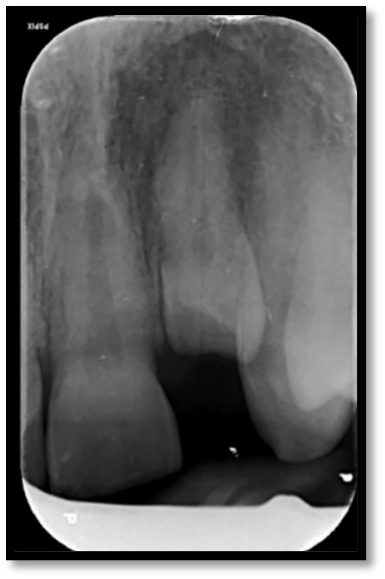

Internal resorption management

Open/Immature apex management and internal whitening

Pre-op

Procedure Photos